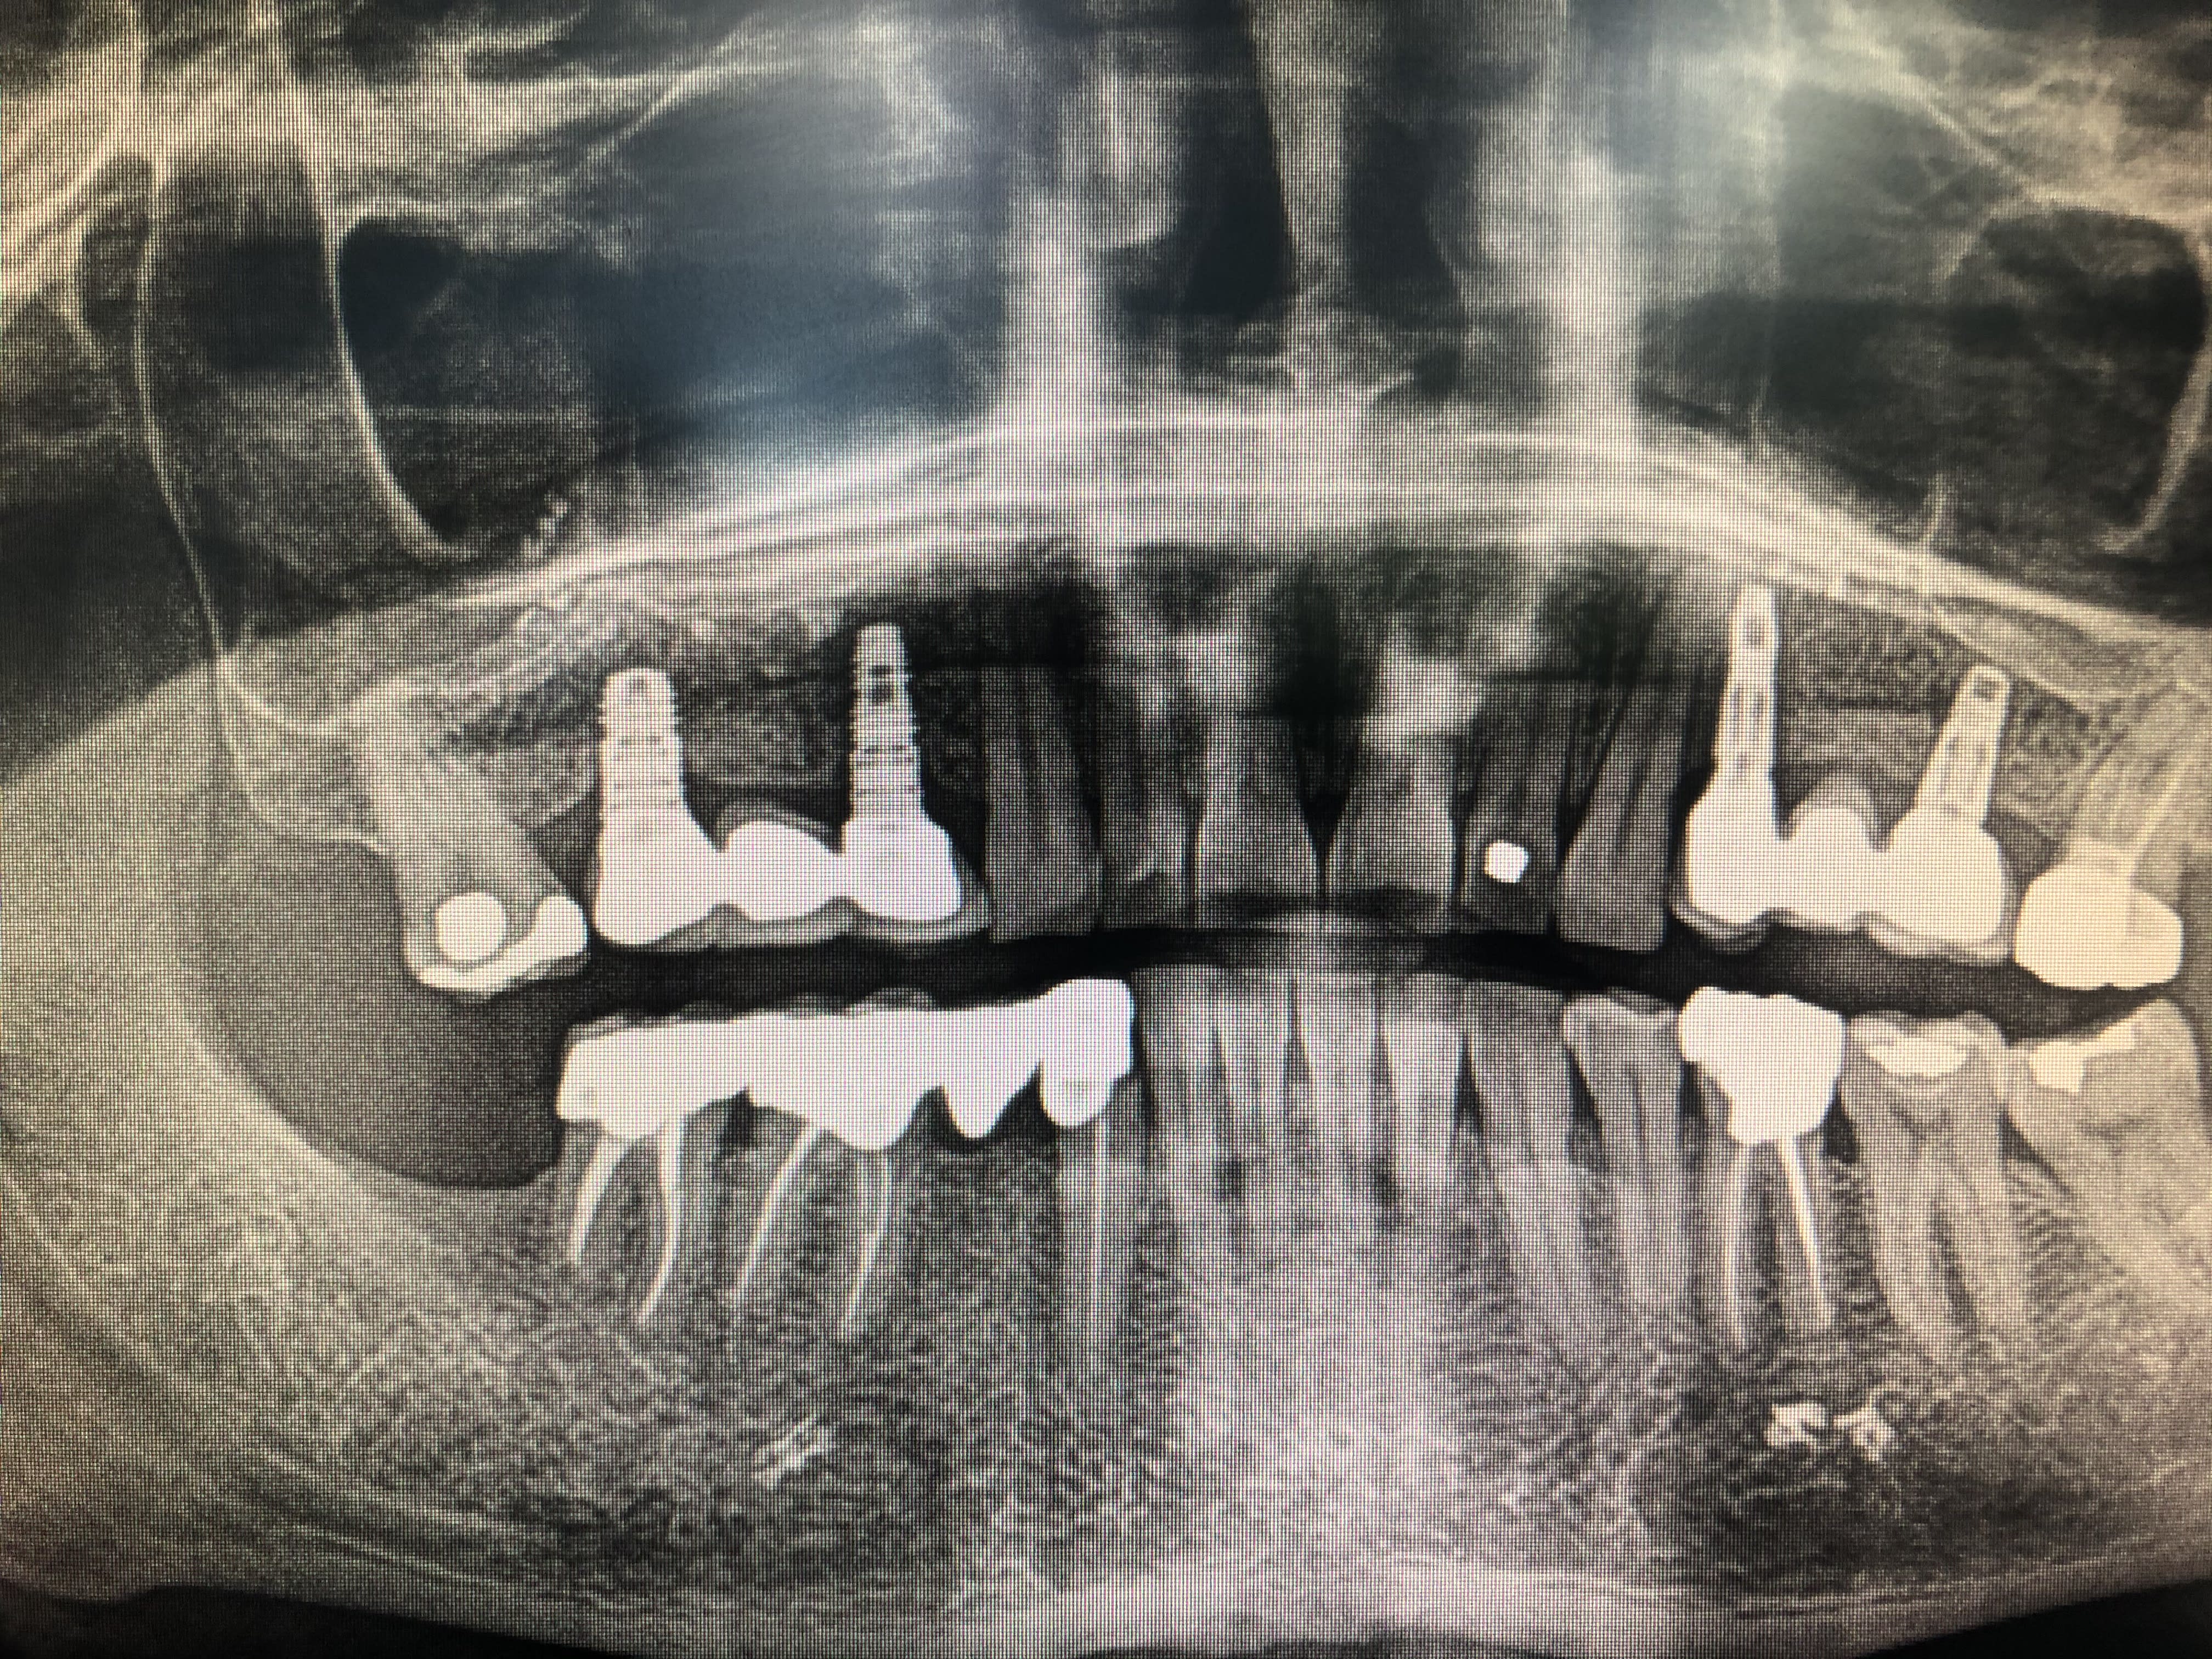

Bjr, j'ai besoin d'un coup de pouce pour m'identifier les implants du bridge en secteur 1.

factoche, Frialit

https://www.spotimplant.com/fr/implants-dentaire/friadent/frialit-2